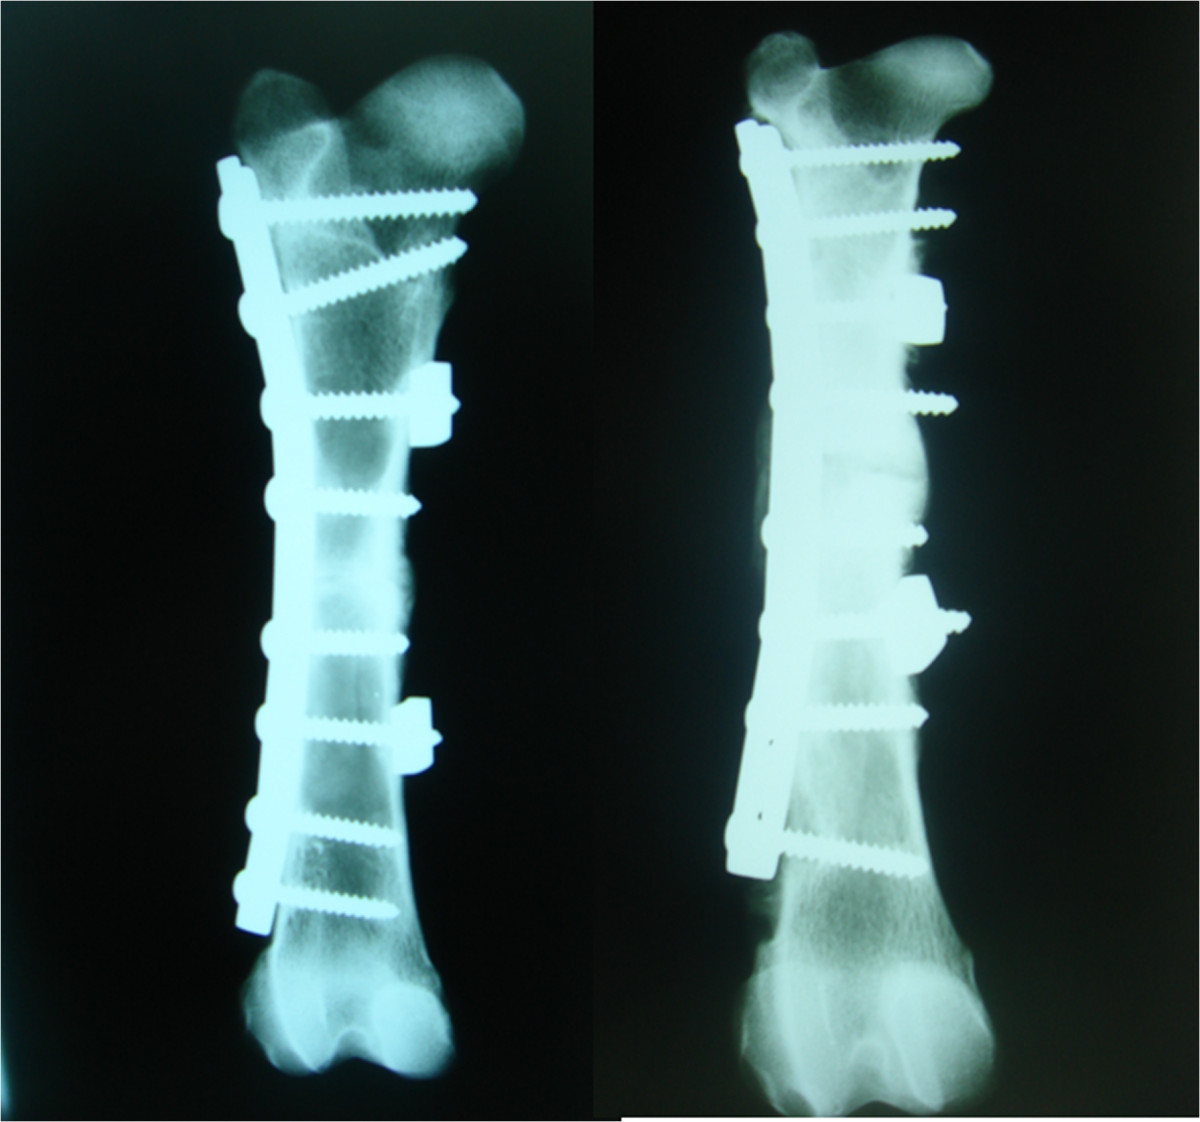

Figure 2.

Two examples of complications in animals operated on without SLE after 8 weeks: absence of callus bridging (left) and loosening of all proximal screws (right).